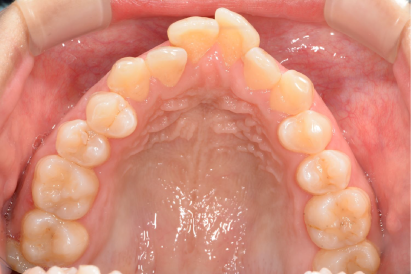

術前

術後

年代、性別

30代、女性

職業

会社役員

主訴

奥歯の詰め物が頻繫に取れる

部位

インビザラインによる全顎矯正と上下顎奥歯8本のセラミック治療

治療期間

1年6ヶ月

矯正費用

95万円

施術説明

患者は10年ほど前に矯正治療の既往がありました。歯並び自体は綺麗になったものの、矯正後に奥歯の詰め物が頻繁に外れて虫歯になり、総合的な治療を希望して来院されました。診察の結果、矯正治療をしているにも関わらず、前歯が噛んでいないので奥歯に過剰な咬合負荷がかかっていることがわかりました。そのため、前歯を咬合させ、奥歯が干渉しないように再度の矯正と奥歯の修復治療が必要と判断しました。治療後には、審美的にも機能的にも満足して頂き、問題なく生活できるようになりました。このような治療は矯正専門医でなくては不可能です。歯のトラブルと歯並びが複合する問題は、複数の専門医が所属する医院を受診して下さい。

副作用・リスク

なし